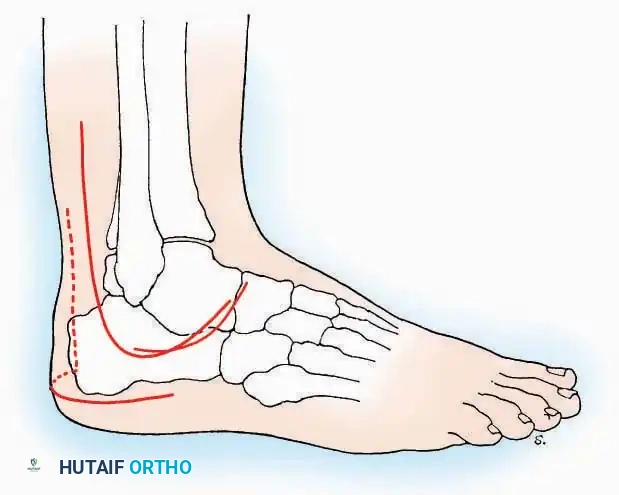

Anterolateral Approach

The anterolateral approach is widely considered the "universal incision" for the foot and ankle. It provides unparalleled access to the ankle joint, the talus, and the majority of the tarsal articulations, while safely avoiding the major anterior neurovascular bundle. The only tarsal joints inaccessible via this route are the naviculocuneiform joints (specifically the medial and intermediate).

Indications: Total talectomy, triple arthrodesis, ankle arthrodesis, and open reduction of complex talar neck fractures.

Surgical Technique:

* Incision: Begin over the anterolateral aspect of the leg, medial to the fibula and 5 cm proximal to the ankle joint line. Carry it distally over the joint, crossing the anterolateral aspect of the talar body and the calcaneocuboid joint, terminating at the base of the fourth metatarsal.

* Superficial Dissection: Incise the superficial fascia and the superior and inferior extensor retinacula down to the periosteum of the tibia and the ankle joint capsule.

* Vascular Ligation: This trajectory usually requires the identification and ligation of the anterolateral malleolar and lateral tarsal arteries.

* Nerve Protection: Retract the skin edges carefully. Identify and protect the intermediate dorsal cutaneous branches of the superficial peroneal nerve (SPN), which frequently cross the distal aspect of this incision.

* Muscle Management: Identify the origin of the extensor digitorum brevis (EDB) muscle on the lateral calcaneus. Divide it in the direction of its fibers, or detach its origin entirely and reflect it distally to expose the subtalar and calcaneocuboid joints.

* Deep Exposure: Retract the extensor digitorum longus (EDL) tendons, the dorsalis pedis artery, and the deep peroneal nerve (DPN) medially. Incise the anterior ankle capsule to expose the tibiotalar joint.

* Tarsal Exposure: Expose the talonavicular joint by dissecting deep to the extensor tendons and incising its capsule transversely. Continue laterally through the capsule of the calcaneocuboid joint. By excising the fat pad within the sinus tarsi (lateral and inferior to the talar neck), the posterior facet of the subtalar joint is brought into direct view.